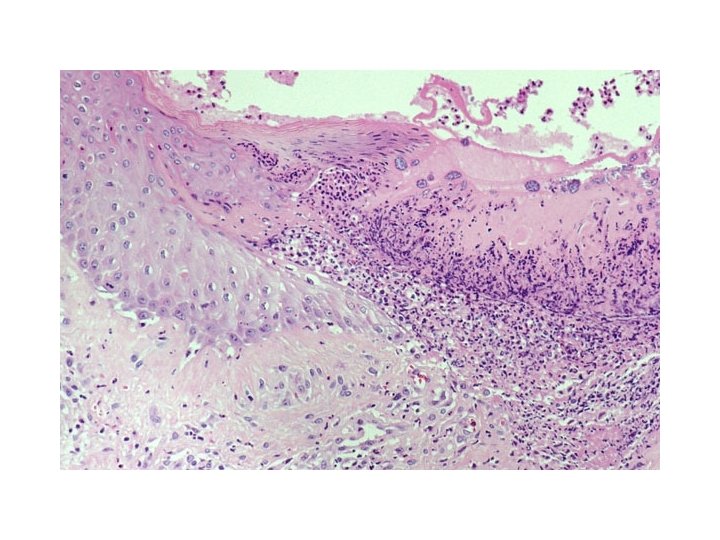

Impetigo

What kind of bacteria do you see?

Which bacterium do you suspect is the cause of the sore throat?

Streptococci Streptococcus pyogenes